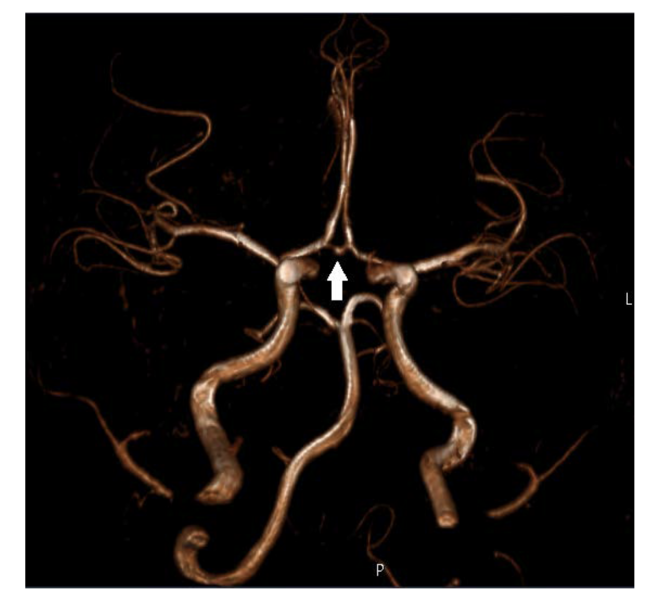

Case 2

A 4-month-old baby boy with Kawasaki disease presented with early onset bilateral coronary artery aneurysms (the largest in the proximal region of the anterior descending artery measuring 6.0 mm (Z-score of +16.22). He displayed clinical improvement on intravenous immunoglobulin, but the coronary artery lesions persisted. Six months post admission, a coronary artery angiogram showed only mild right coronary artery enlargement.

At the age of 10 years, a new coronary artery angiogram (Figure 2) showed a severe stenotic lesion in the middle segment of the right coronary artery, as well as a rich arterial collateral network arising from this vessel. The patient is asymptomatic on double anti-platelet therapy. A treadmill stress test and dobutamine stress echocardiography showed no evidence of cardiac ischemia.